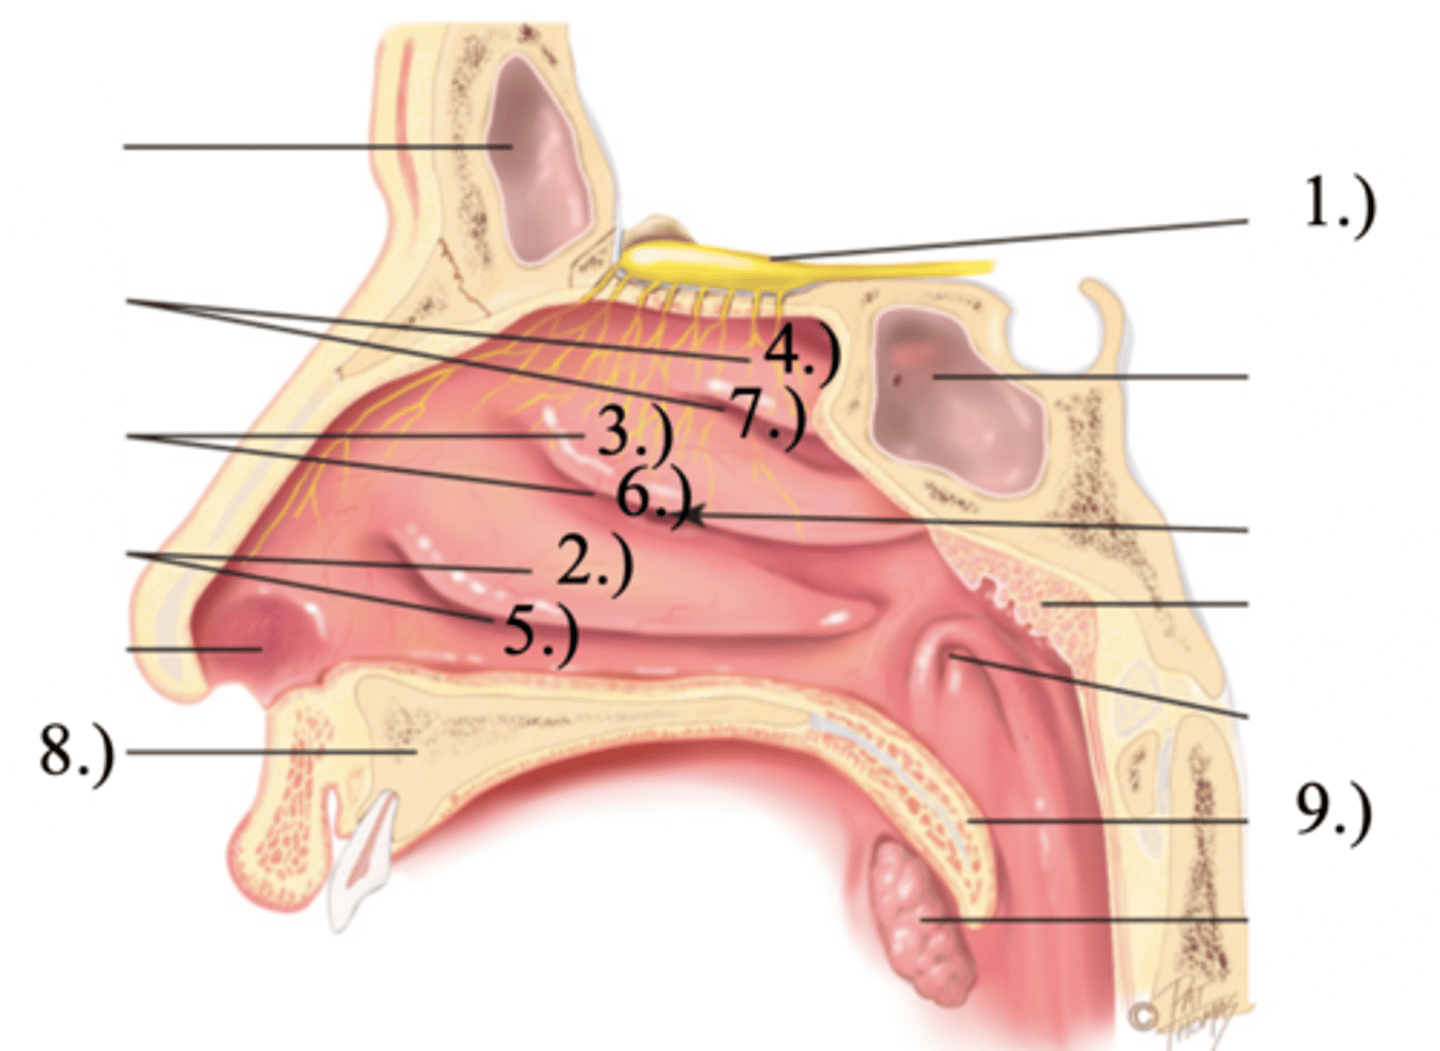

Turbinates (Conchae)

- There's an inferior, middle, and superior one (2.), 3.), 4.))

Olfactory Region

A dime-sized area at the top of each nasal cavity that houses sensors responsible for smell (1.))

Hard (Bony) Palate

Anterior palate portion that is supported by the palatine processes of the maxillae and the palatine bones (8.))

Meatuses

- Constricted passageways in the nasal cavity that produce air turbulence

- There's an inferior, middle, and superior one

(5.), 6.), 7.))

Soft Palate

Posterior palate portion, not supported by bone (9.))